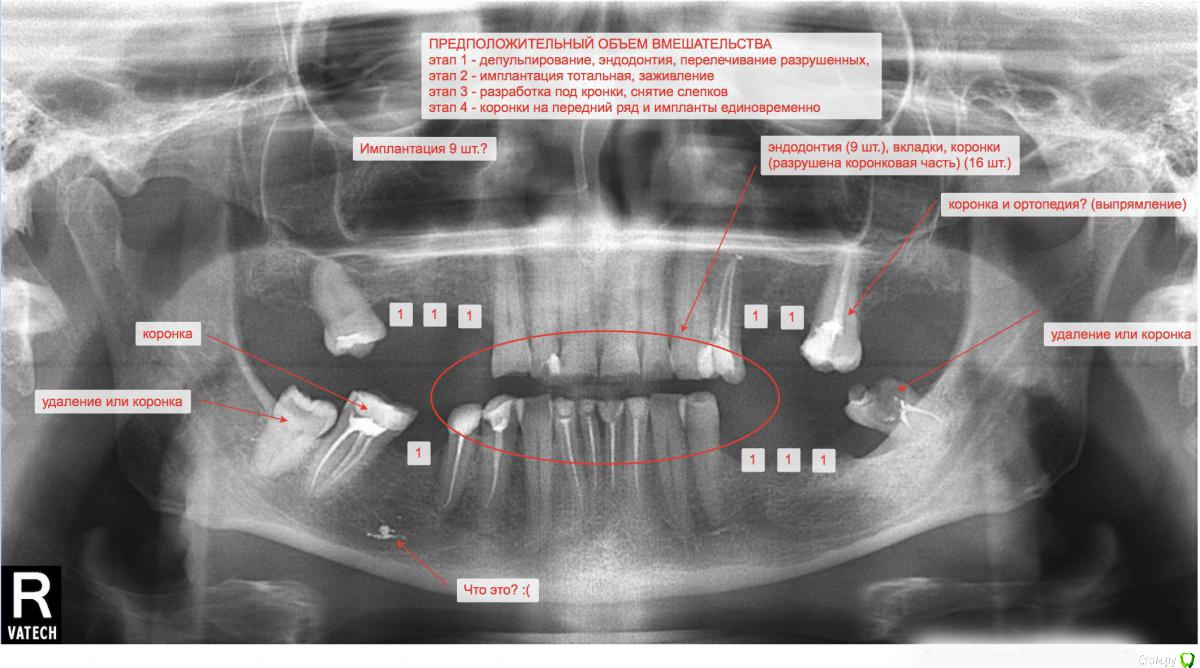

arinasmirn74@gmail.com Опубликовано 1 апреля, 2019 Поделиться Опубликовано 1 апреля, 2019 (изменено) Здравствуйте!Получила наконец панорамный снимок брата (планируется третий подход к снаряду после череды неудач, как то неудачная попытка съемного протезирования). Прошу прокомментировать, если возможно, этапность работ по восстановлению жевательной функции, варианты и что вообще делать? Передние без кариеса, но коронковая часть разрушена почти до десны, жевательных почти нет, что есть искривлено.Что может означать пятно в проекции давно удаленного зуба слева на снимке? Изменено 1 апреля, 2019 пользователем arinasmirn74@gmail.com Ссылка на комментарий

kramer Опубликовано 1 апреля, 2019 Поделиться Опубликовано 1 апреля, 2019 Пятно - пломбировочный материал. Если нужен несъемный протез, надо ставить имплантаты в боковых отделах. Зубы покрыть коронками. Ссылка на комментарий

arinasmirn74@gmail.com Опубликовано 1 апреля, 2019 Автор Поделиться Опубликовано 1 апреля, 2019 (изменено) Пятно - пломбировочный материал. Если нужен несъемный протез, надо ставить имплантаты в боковых отделах. Зубы покрыть коронками. Спасибо!Я расписала на снимке план работ, как я его себе представляю, похоже на правду? Изменено 1 апреля, 2019 пользователем arinasmirn74@gmail.com Ссылка на комментарий

kramer Опубликовано 1 апреля, 2019 Поделиться Опубликовано 1 апреля, 2019 Ну приблизительно) Потребуется более детальное обследование. КТ, фотографии, гипсовые модели, wax-up и т.д. Ссылка на комментарий

Дмитрий Л. Опубликовано 1 апреля, 2019 Поделиться Опубликовано 1 апреля, 2019 Эндодонтию передних оставьте напоследок, сначала нужно восстановить прикус жевательных зубов, при чём не откладывать, так как в дальнейшем вероятно появятся проблемы с суставом. Ссылка на комментарий

arinasmirn74@gmail.com Опубликовано 1 апреля, 2019 Автор Поделиться Опубликовано 1 апреля, 2019 Эндодонтию передних оставьте напоследок, сначала нужно восстановить прикус жевательных зубов, при чём не откладывать, так как в дальнейшем вероятно появятся проблемы с суставом.то есть имплантация сначала, а передние потом? Они разрушаются на глазах, на снимках не очень это видно, но там у некоторых уже нет коронковой части практически, сколы . Ссылка на комментарий

Bier Опубликовано 1 апреля, 2019 Поделиться Опубликовано 1 апреля, 2019 похоже на правду 8ки внизу удалить. 47й и 17й поднять (выпрямить)Там где 3 имплантата у Вас на плане, можно обойтись 2мя, иногда это даже лучше, чем 3Ну и зубы не нужно депульпировать и под вкладки, протезируйте безметалловой керамикой. Они останутся живыми и еще много лет вам прослужат. 1 Ссылка на комментарий